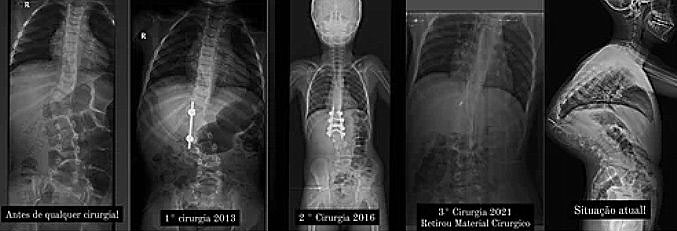

Procedimentos cirúrgicos que Murilo já passou.

O problema foi descoberto em 2008, quando Murilo tinha apenas quatro meses, ou seja, que tinha escoliose congênita, através de um problema de saúde que sofreu e precisou passar por uma cirurgia no intestino. Desde então, já passou por três cirurgias.

Este é o custo pagar uma cirurgia que pode salvar a vida do garoto, que sofre de uma cifoescoliose congênita, com uma curvatura de 127 graus na coluna vertebral.

Ele tem uma coluna que ultrapassa 100 graus de curvatura